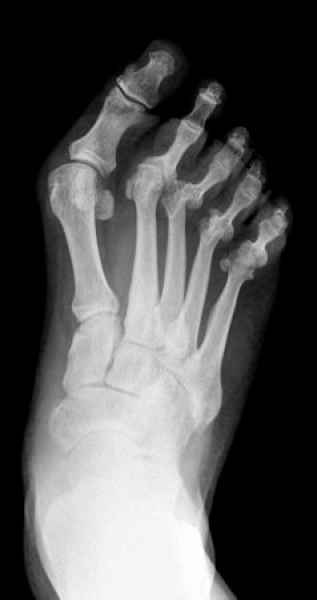

El pie es el órgano distintivo y característico de la especie humana, la única criatura que marcha erguida. El pie es una muy compleja estructura de arquitectura perfecta, adaptado a su función de apoyo, traslación, salto, con una riquísima sensibilidad que le permite detectar las más leves imperfecciones del suelo para estabilizar la marcha.

Tanto la estructura del pie como su funcionalismo que es la marcha, pueden ser asiento y manifestación respectivamente de alteraciones locales ó sistémicas, por lo que su cuidadoso examen resulta de extrema utilidad diagnóstica.